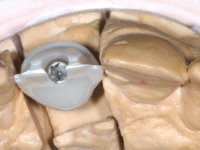

After the impression of the implant using a double-mix technique with double viscosity and the collection of shape and color information by the ceramist, we proceed with the work. In the model, a syn octa was placed over the implant, and a screw was placed on it to assess its emergence in relation to the incisal edge. Then, an adequate emergence profile in the artificial gingiva was prepared. A abutment with characteristics suitable for overbite and simultaneously capable of receiving a veneer was waxed on top of this scenario. This waxing gave rise to the manual milling of a very personalized abutment. An infrastructure in Zr was also made for the veneer with a very great adaptation to the abutment. On this infrastructure ceramics were placed. Ceramic fluorescence sought to compensate for the lack of fluorescence that Zr had and obviously further customize the aesthetics. The adhesive bridge was removed and the definitive work was placed. The syn octa was initially tightened with 35 N to the implant and then the Zr abutment was tightened over the syn octa with 15 N. The access hole was plugged and then the veneer was cemented with resin-reinforced glass ionomer. After 15 years, the patient returned to the consultation with tooth mobility. Fortunately, nowadays we have the possibility of having dynamic tightening wrenches that allow tightening screws with greater inclinations. An access cavity was made without damaging the incisal edge of the veneer. Tightening was done with a dynamic wrench with 15 N torque. The hole was covered with Teflon and filled with composite resin. This solution allowed the problem to be solved in a simple and economical way.